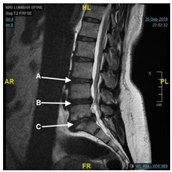

| 3. | According to the report (Image), can you determine the location of the L5 S1 in the following image![]() | a. A b. B c. C d. I do not know | 1 |